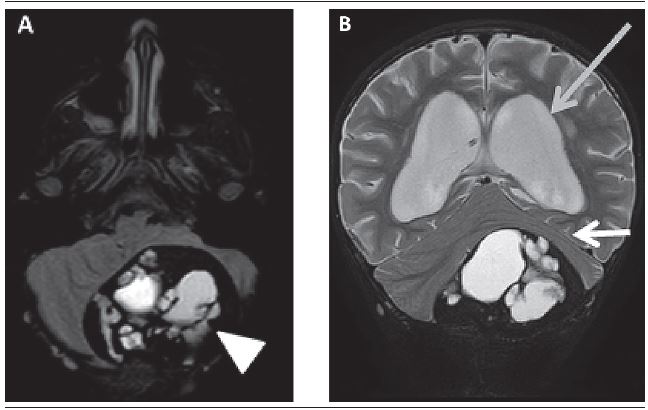

A 4-year-old male patient, with a headache beginning 18 months before, progressively worsening, associated with loss of balance, difficulty walking - short steps - decreased appetite, progressing to vomiting and frequent blackouts, especially during his school activities. Normal electroencephalogram (EEG). A magnetic resonance imaging (MRI) was performed and demonstrated (Figures 1 and 2):

extra-axial mass lesion in the posterior aspect of the posterior fossa on the left, measuring 7.5 × 5.8 × 5.2 cm, crossing occipital bone posterior and inferior aspects, with projection to the adjacent soft tissues, well-defined and extensive hemorrhage inside;

intense contrast enhancement at the periphery of the lesion;

compression of cerebellar hemispheres and distorts the fourth ventricle with severe hydrocephalus upstream.